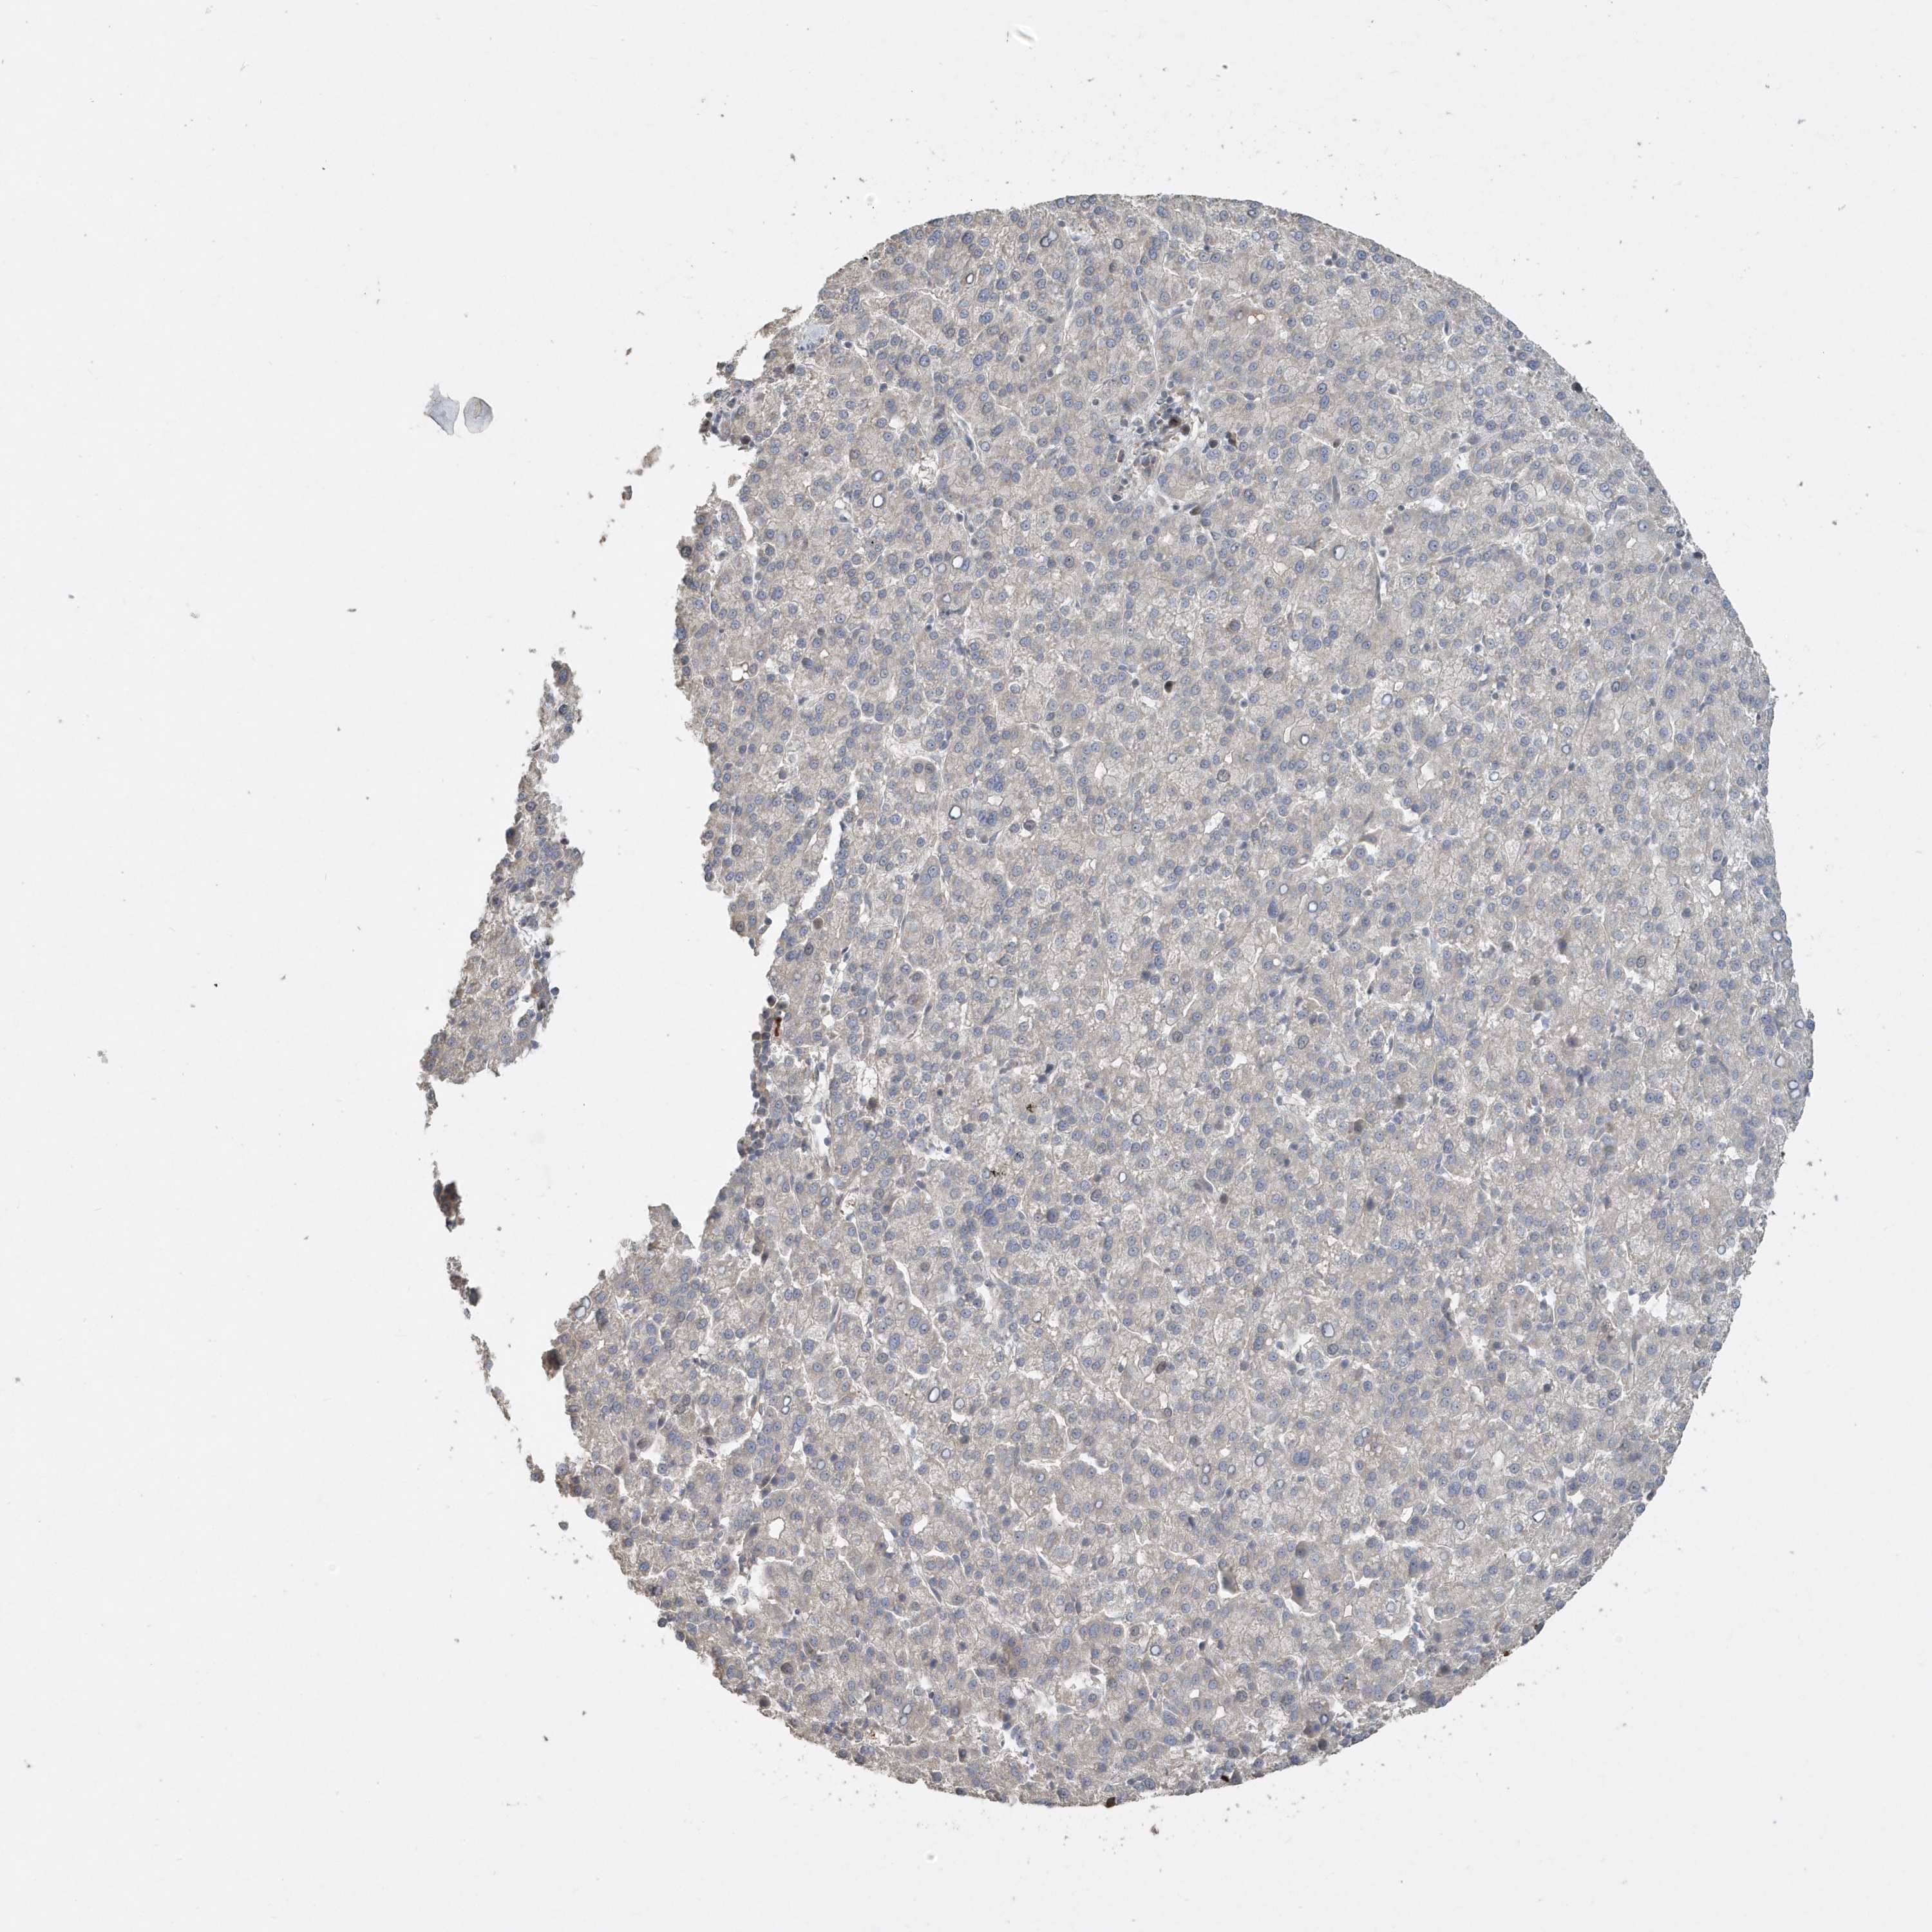

LIVER CANCER - Protein expressioni

A mouse-over function shows sample information and annotation data. Click on an image to view it in a full screen mode. Samples can be filtered based on level of antibody staining by selecting one or several of the following categories: high, medium, low and not detected. The assay and annotation is described here.

Antibody stainingi

Antibody staining in the annotated cell types in the current human tissue is reported as not detected, low, medium, or high, based on conventional immunohistochemistry profiling in selected tissues. This score is based on the combination of the staining intensity and fraction of stained cells.

Each image is clickable and will lead to virtual microscopy that enables deeper exploration of all samples and also displays staining intensity scores, fraction scores and subcellular localization as well as patient and tissue information for each sample.

Antibody HPA036261

Antibody HPA036262

Staining

High

Medium

Low

Not detected

Intensity

Strong

Moderate

Weak

Negative

Quantity

>75%

75%-25%

<25%

None

Location

Nuclear

Cytoplasmic/membranous

Cytoplasmic/membranous,nuclear

Cholangiocarcinoma

Carcinoma, Hepatocellular, NOS